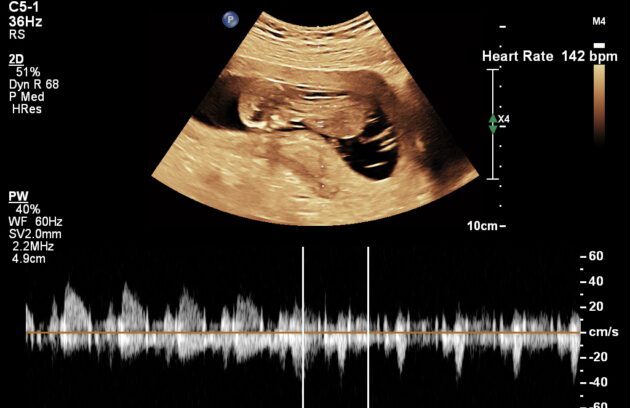

🔹 Pregnancy Confirmation Scan

Pregnancy Confirmation Scan is the first ultrasound performed to confirm pregnancy and detect the baby’s heartbeat. It helps determine gestational age, location of pregnancy (intrauterine), and rule out conditions like ectopic pregnancy. If you suspect pregnancy, a pregnancy ultrasound in Kathmandu ensures early confirmation and peace of mind.